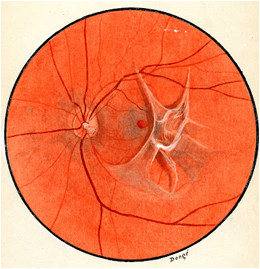

La membrane épirétinienne (MER) peut également s’appeler membrane épimaculaire (MEM). Il s’agit d’une couche de cellules qui se forme à la surface de la rétine au niveau de la macula on l’on retrouve le centre de la vision.

On peut schématiser une membrane épirétinienne comme une fine couche de cellophane qui serait déposée sur la rétine, avec le temps celle-ci peut s’épaissir, se contracter et ainsi déformer la macula.

Le diagnostic d’une membrane épirétinienne se fait grâce à l’examen de la macula au fond d’œil mais surtout grâce à l’OCT. Il est absolument essentiel. Il permet d‘évaluer l’importance de la membrane au fond d’œil et également l’importance de la déformation de la macula.